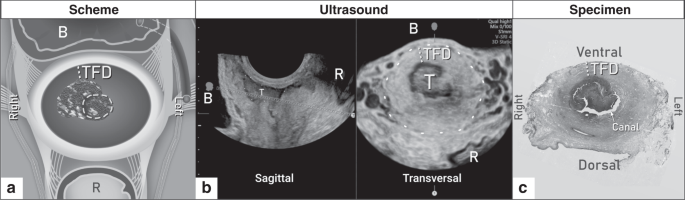

All patients underwent a standardised US examination by an experienced examiner (level 3 according to the recommendations for the practice of the medical US of the European Federation of Societies for Ultrasound in Medicine and Biology);26 the methodology was described in more detail elsewhere.27 Using the real-time 2D-US (greyscale and power Doppler), the examiner followed a standardised protocol and evaluated the presence of the tumour, the tumour size in three diameters, the distance between the cranial pole of the tumour and the internal cervical os, the integrity of the pericervical ring, the involvement of parametria and adjacent organs and the retroperitoneal LNs (Supplementary Table S1). TFD was measured on a transversal plane as a minimum distance of uninvolved stroma between the tumour and pericervical ring (dense hyperechogenic layer surrounding the cervix) (Fig. 2). If no residual tumour was found by imaging after conisation, TFD was calculated as half of the cervical transversal diameter. A standardised US protocol was completed in the web-based central database, data were locked after an examination, and the database did not allow any subsequent changes. When clinically indicated, or if any limitation of US was encountered, the appropriate complementary imaging method was completed and reviewed by an experienced radiologist dedicated to gynaecologic oncology.

The method used for the assessment of individual markers is reported in the article as “P” for pathology or “I” for imaging. Together, 15 prognostic markers were evaluated, including age, 11 tumour-related and three LN status-related ones (LN positivity, number of positive LNs; type of metastasis in LN). Amongst tumour-related factors, seven were related to tumour size assessment: stage (P), largest tumour size (P and I), tumour volume calculated by the formula for ellipsoid from pathological measurement (P), largest tumour size binarised (P), depth of stromal invasion (DSI) (P), minimal TFD (I) defined as the minimal uninvolved stroma between the tumour and pericervical ring (dense hyperechogenic layer on ultrasound while hypointense layer on MRI) on either side of the cervix, minimal TFD binarised (I); and four markers related to pathology or local disease spread: LVSI, tumour type, grade, parametrial invasion (P). Gynaecologic Oncology Group score (GOG score) was calculated according to the GOG criteria combining LVSI status, DSI and tumour size.3